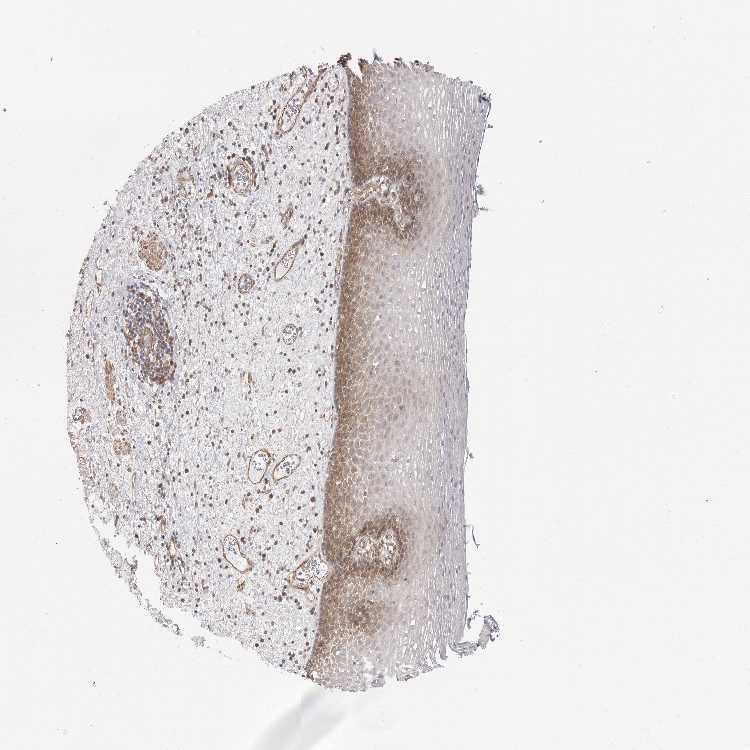

ESOPHAGUS - Antibody stainingi

Antibody staining in the annotated cell types in the current human tissue is reported as not detected, low, medium, or high, based on conventional immunohistochemistry profiling in selected tissues. This score is based on the combination of the staining intensity and fraction of stained cells.

Each image is clickable and will lead to virtual microscopy that enables deeper exploration of all samples and also displays staining intensity scores, fraction scores and subcellular localization as well as patient and tissue information for each sample.

Antibody HPA027262Antibody HPA078737

Squamous epithelial cells MediumNot detected